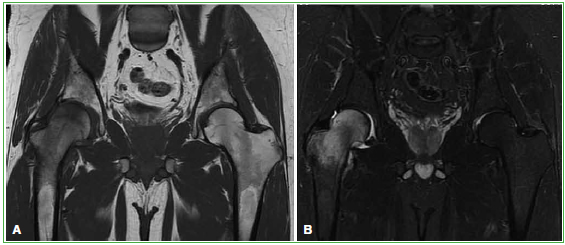

Figura 7.

Resonancia magnética de cadera derecha, corte coronal en secuencias potenciadas en T1 (A) y STIR (B). Se observa edema óseo (aumento de la señal) que afecta a la cabeza y el cuello del fémur, asociado a derrame articular en un paciente de 30 años.